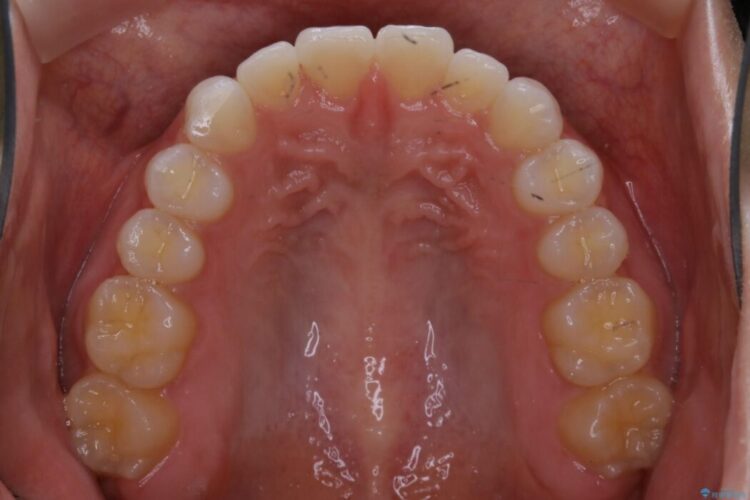

半年という短期間でスピード治療が完了しました。

治療期間、治療後の出来ともに大変ご満足いただけました。